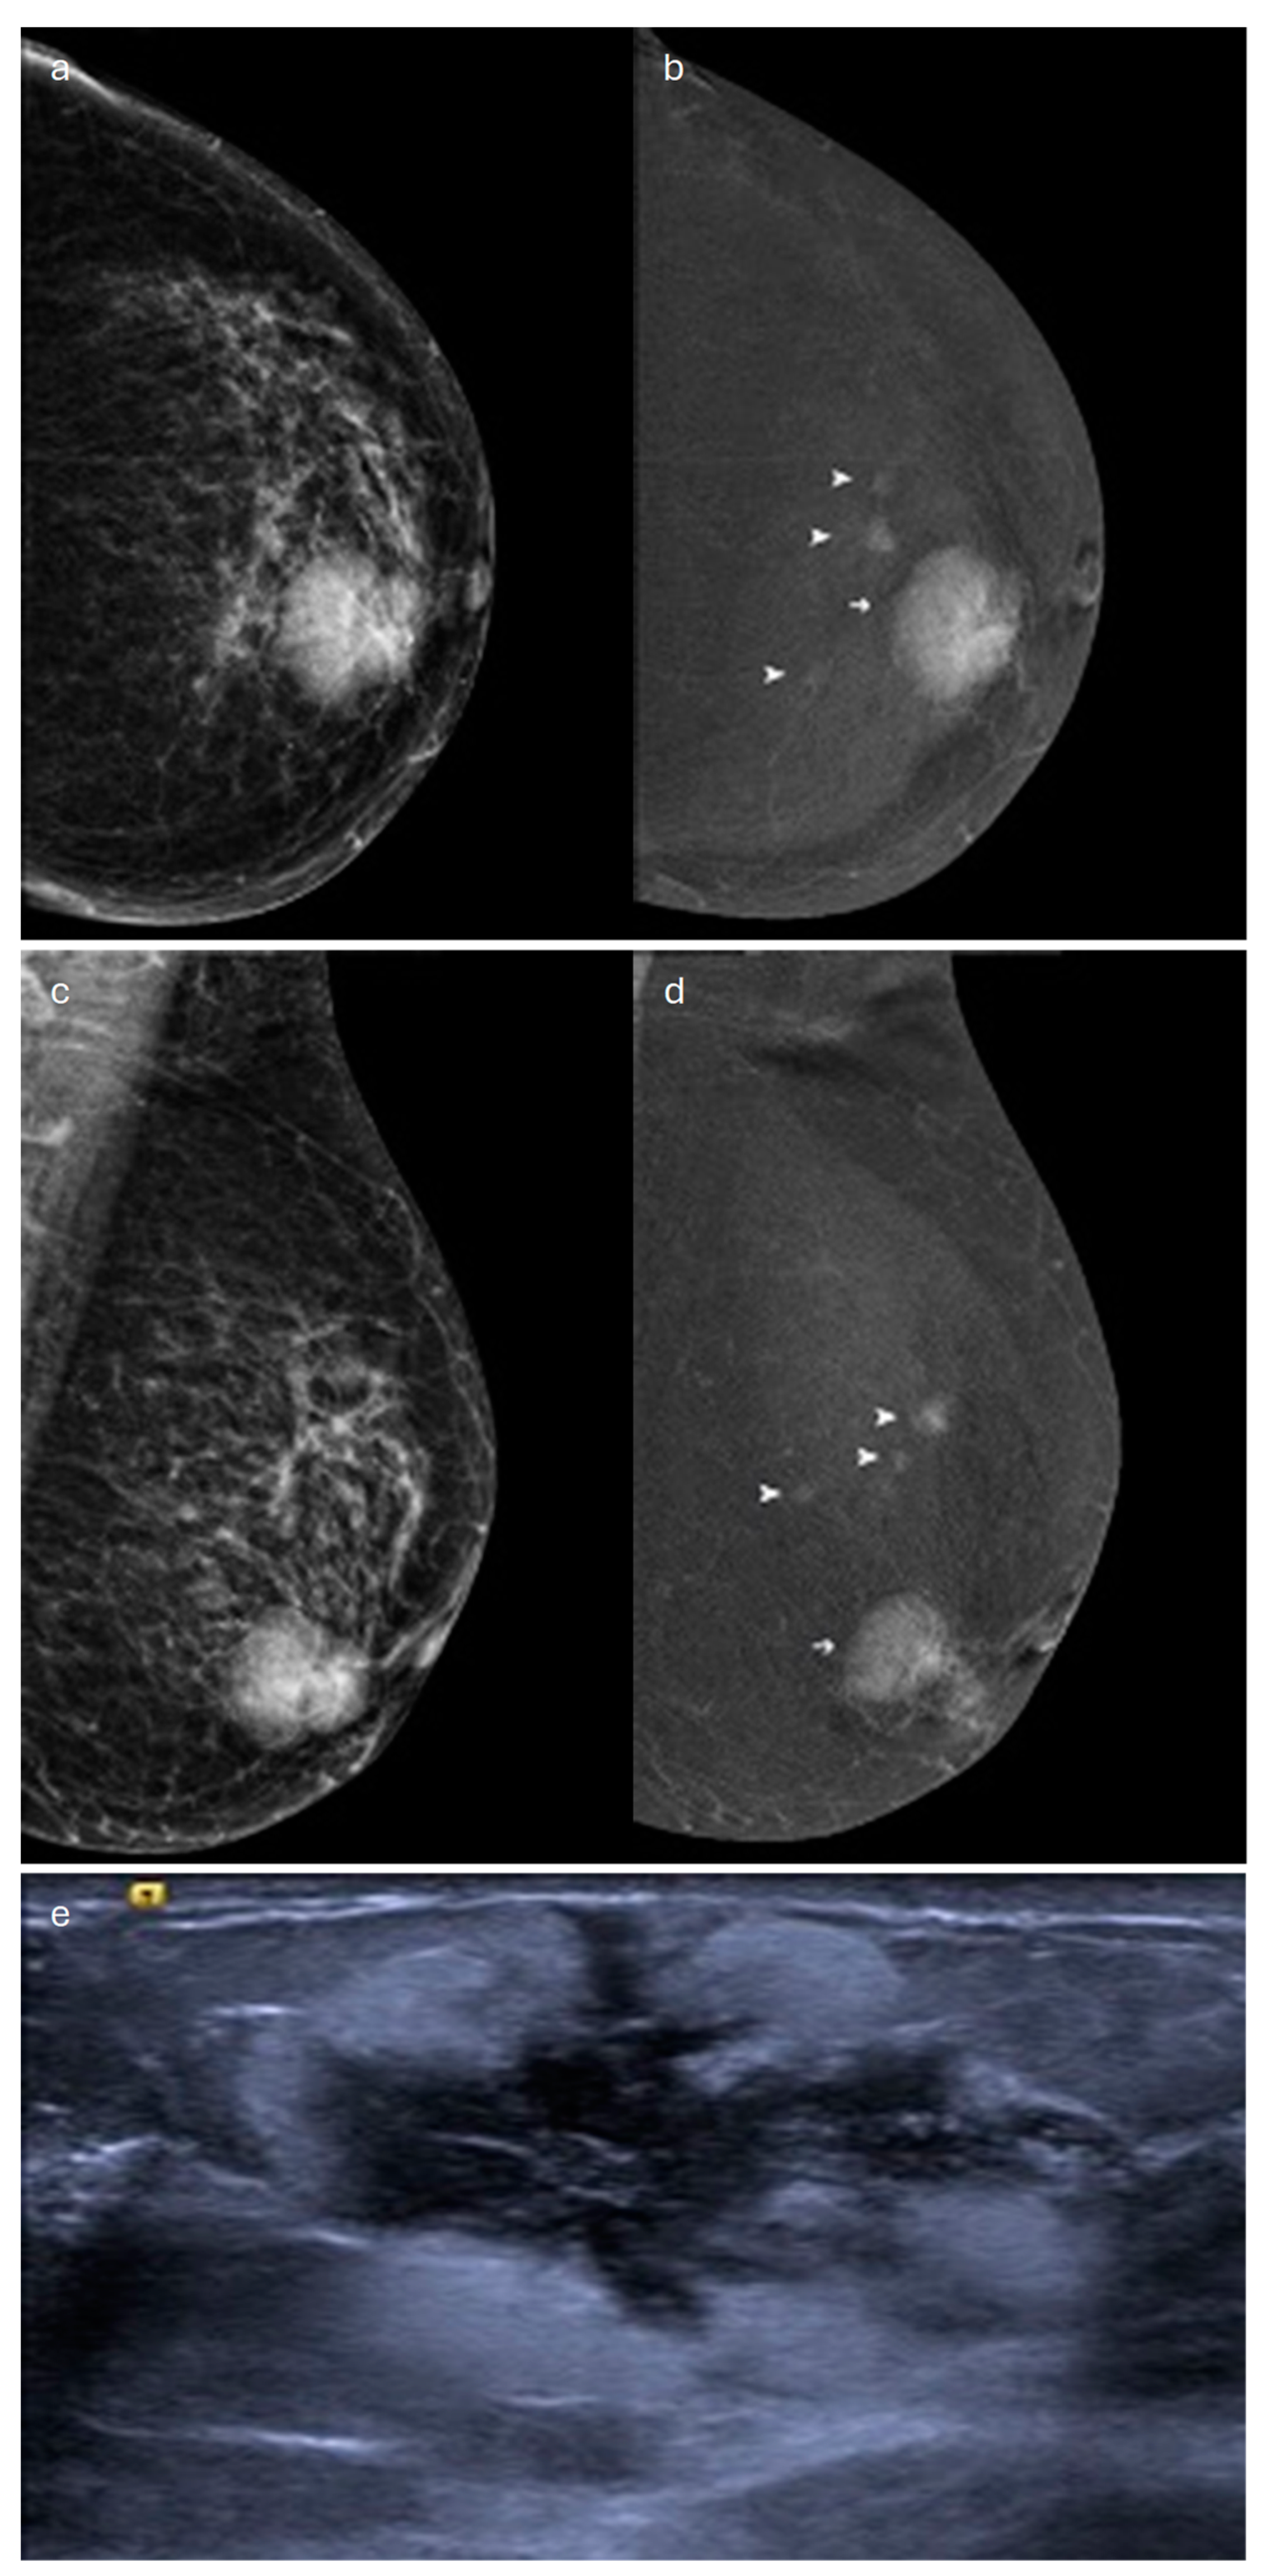

2. Lobular (Classic, Pleomorphic and Florid Types)